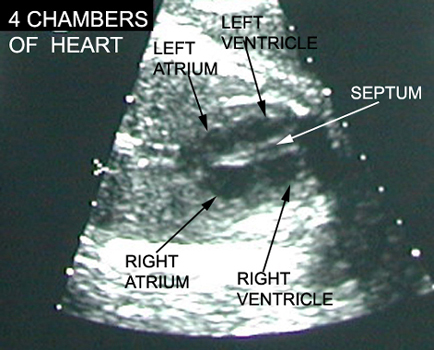

Fetal Heart |

|

Heart Chambers |

|